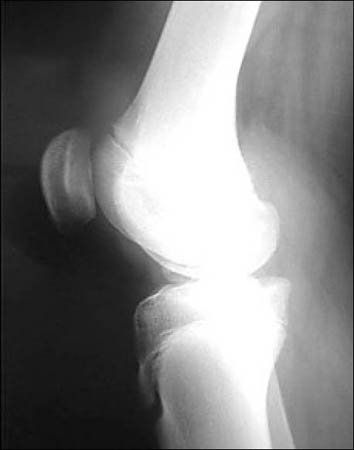

Rx con incidencias de frente y perfil de rodilla. (Fig. 1)

Figura 1: Rx perfil, rótula alta, hallazgo: encondroma de fémur distal.